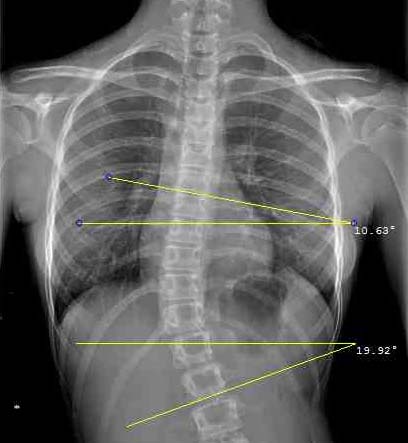

The Cobb angle is found on radiographs by placing the inclinometer on the spine’s most tilted vertebra above the curve’s apex and then on the most tilted vertebra beneath the apex. The rod bubble has to be centred to determine the angle of inclination. The Cobb angle is found adding the two angles together.

The inclinometer is very useful for quickly identifying the most inclined vertebrae on the X-ray.